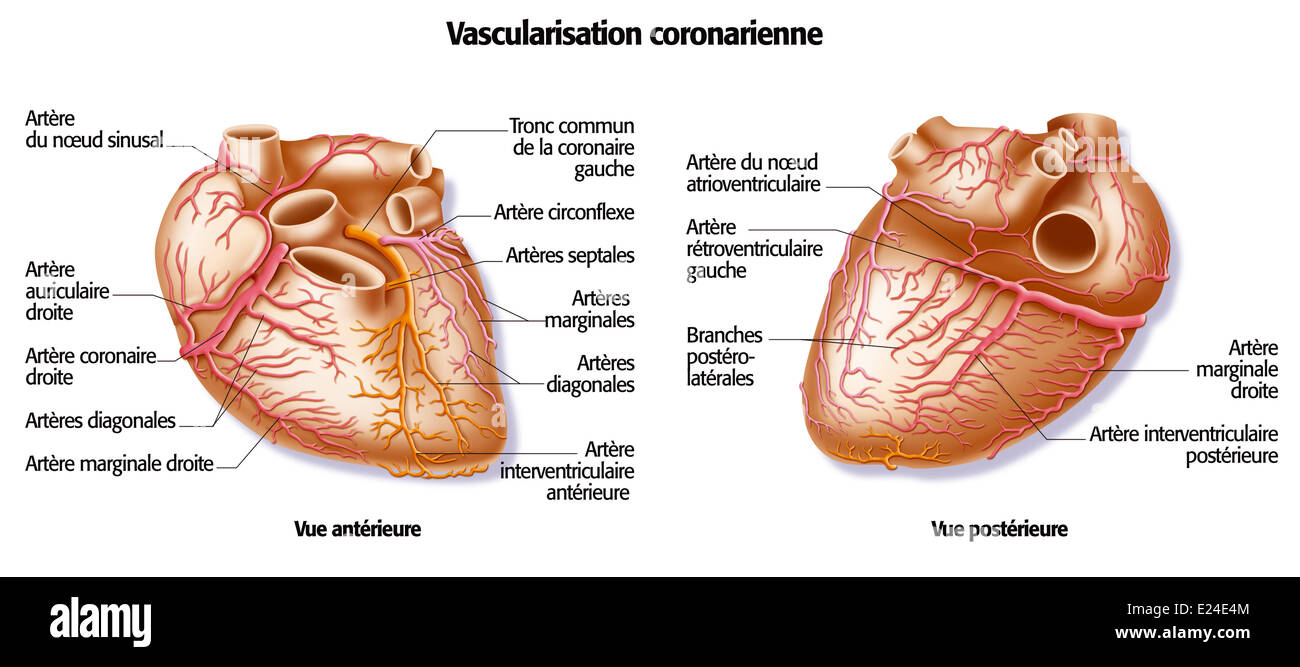

Heart, I Stock Photohttps://www.alamy.com/image-license-details/?v=1https://www.alamy.com/stock-photo-heart-i-70169700.html

Heart, I Stock Photohttps://www.alamy.com/image-license-details/?v=1https://www.alamy.com/stock-photo-heart-i-70169700.htmlRME24E4M–Heart, I